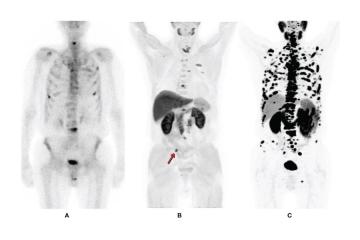

Expert Radiologists in Mumbai - Picture This

Mumbai, India

Finding truly subspecialized radiologists in Mumbai — doctors who go beyond general reporting and offer deep clinical insight — is harder than most patients realize. Picture This has been setting that standard since 1969, building one of the most trusted and comprehensive diagnostic imaging centers in India. Their team of subs...